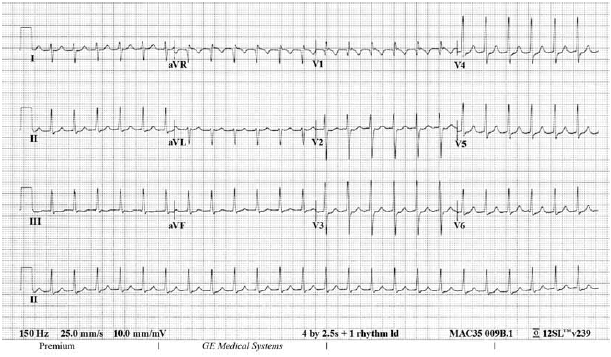

Uma jovem de vinte e dois anos de idade, previamente hígida, ingressou no pronto-socorro apresentando um quadro de palpitações taquicárdicas, de início súbito, havia uma hora. Ela negou outros sinais ou sintomas. Ao exame físico, a paciente apresentava-se eupneica e acianótica, em bom estado geral, com pressão arterial de 116 mmHg × 72 mmHg, frequência respiratória de 24 irpm, frequência cardíaca de aproximadamente 150 bpm e ritmo cardíaco regular em dois tempos e sem sopros. Não foram constatadas outras alterações. O seguinte eletrocardiograma (com calibração padrão) mostrado na figura foi realizado na sua chegada ao serviço de pronto atendimento.

O tratamento inicial de escolha para a paciente do caso clínico em questão consiste na administração intravenosa de amiodarona.